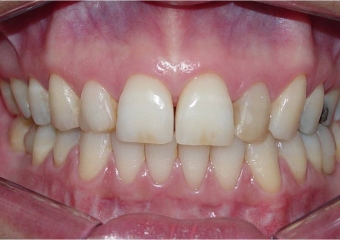

Mordida inicial

Mordida final